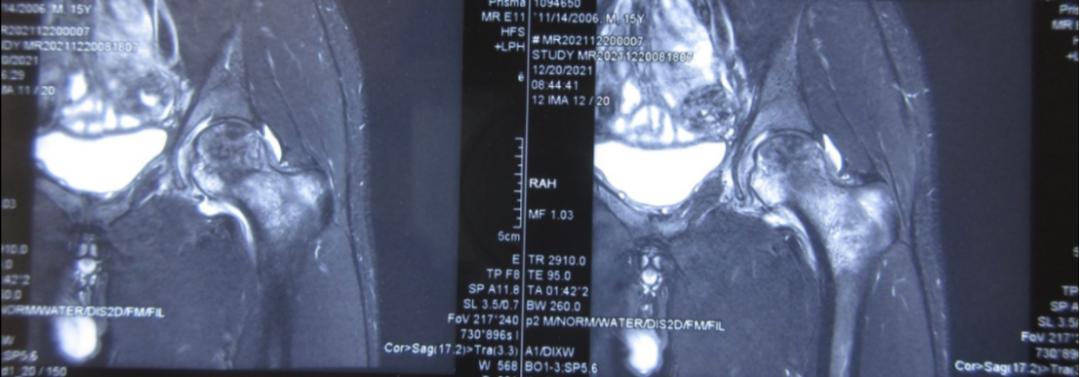

抱着对诊断的不相信,阿峰家人多方打听,了解到何伟教授是国内知名的股骨头坏死专家,便带着阿峰来到何伟教授的门诊。何伟教授从病史中了解到阿峰既往没有明显髋部外伤史,也没有服用激素史与酗酒史;查体发现阿峰行走跛行、下蹲困难、髋关节外展、内外旋活动受限,X光片显示左股骨头内密度不均、塌陷,磁共振(MR)提示左股骨头大范围坏死、左股骨近端骨髓水肿。根据病史、临床检查与影像资料,股骨头坏死的诊断已经明确,而且已经发展到3期(塌陷),保髋到了刻不容缓的时机,同时阿峰数月前曾发生过严重感染,髋关节有无合并感染,也需要尽快明确,于是何伟教授建议阿峰尽快办理入院。

磁共振检查结果提示:左股骨近端骨髓水肿